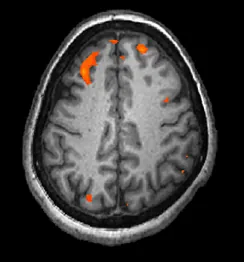

W rezonansie magnetycznym (ang. magnetic resonance imaging (MRI)) uczestnik jest umieszczany wewnątrz urządzenia wytwarzającego silne pole magnetyczne. Pole to porządkuje atomy wodoru w komórkach. Po wyłączeniu pola atomy te wracają do pierwotnego położenia, emitując przy tym pole elektromagnetyczne. Tkanki o różnej gęstości wysyłają sygnały o różnym natężeniu, które komputer przetwarza i obraz badanego obszaru wyświetla na ekranie monitora. Czynnościowy rezonans magnetyczny (ang. functional magnetic resonance imaging (fMRI)) działa na tej samej zasadzie, ale pokazuje zmiany aktywności mózgu w czasie, śledząc przepływ krwi i poziom wysycenia jej tlenem. fMRI dostarcza bardziej szczegółowych obrazów budowy mózgu, z większą dokładnością czasową niż w przypadku techniki PET (Ilustracja 3.28). Przy tak dużym poziomie szczegółowości MRI i fMRI często wykorzystuje się do porównywania mózgów osób zdrowych z mózgami osób ze zdiagnozowanymi zaburzeniami psychicznymi. Takie porównanie pomaga określić strukturalne i czynnościowe różnice między populacjami ludzi zdrowych i chorych.

Obraz pokazuje tkankę mózgową w kolorze szarym, ale niektóre, niewielkie obszary świecą na czerwono.

Ilustracja 3.28 fMRI pokazuje zmiany aktywności mózgu w czasie. Rysunek przedstawia pojedynczą klatkę zarejestrowaną w czasie badania. (Źródło: modyfikacja pracy Kim J., Matthews N.L., Park S.).